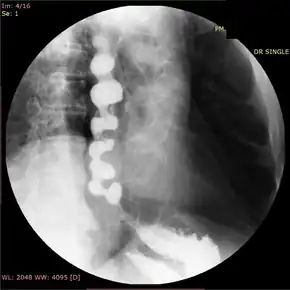

![]() | |

| Jackhammer esophagus with normal distal latency on esophageal high-resolution manometry | |

In people who have dysphagia, testing may first be done to exclude an anatomical cause of dysphagia, such as distortion of the anatomy of the esophagus. This usually includes visualization of the esophagus with an endoscope, and can also include barium swallow X-rays of the esophagus. Endoscopy is typically normal in patients with nutcracker esophagus; however, abnormalities associated with gastroesophageal reflux disease, or GERD, which associates with nutcracker esophagus, may be seen.[16] Barium swallow in nutcracker esophagus is also typically normal,[6] but may provide a definitive diagnosis if contrast is given in tablet or granule form. Studies on endoscopic ultrasound show slight trends toward thickening of the muscularis propria of the esophagus in nutcracker esophagus, but this is not useful in making the diagnosis.[17]